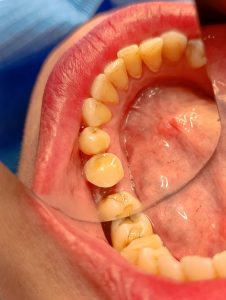

Τελική εικόνα μετά την ανασύσταση του δοντιού